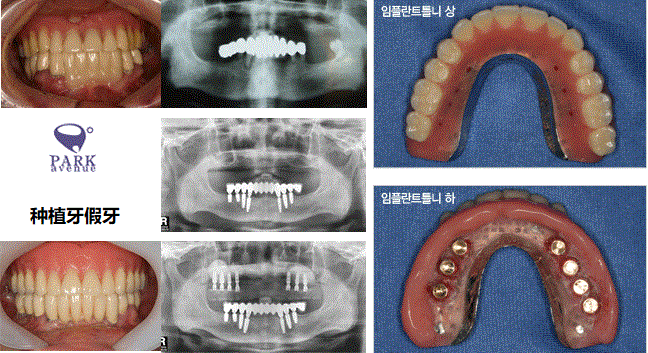

2. 假牙性种植牙

全口缺牙的话特别通过种植牙制作比基准使用的假牙方便和性能好的假牙。颚骨前面部分2~4个左右种植牙植立后安装假牙。

比基准的假牙不容易脱落,咬力也更好,而且省钱就很好的办法。